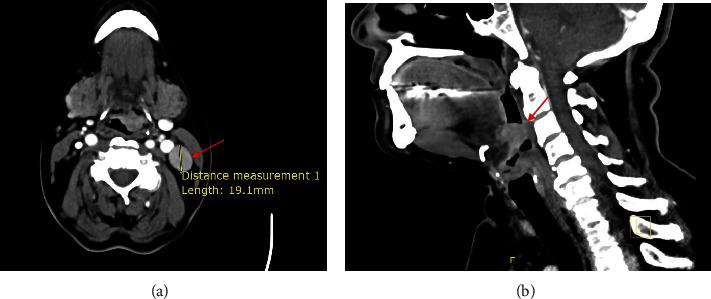

Neuroendocrine neoplasms (NENs) are rare in the head and neck region, with the larynx being the most common site. To date, nearly 700 cases of laryngeal neuroendocrine carcinoma (NEC) have been reported in the literature, with an estimated incidence as low as 0.23%. This type of cancer is more prevalent among men aged 50-83 who are heavy smokers. NENs encompass paragangliomas and epithelial neoplasms. The latter categories include neuroendocrine tumors, or typical carcinoids, and NECs, or atypical carcinoids. Due to their nonspecific and often misleading presentation, and given the rarity of this condition, optimal management lacks standardization. Treatment typically involves a combination of surgery, chemotherapy, and radiotherapy. We present a case of supraglottic laryngeal NEC in a 61-year-old female nonsmoker. The patient underwent endoscopic excision followed by adjuvant radiotherapy.

神经内分泌肿瘤(NENs)在头颈部区域较为罕见,其中喉是最常见的发病部位。迄今为止,文献中已报道了近700例喉神经内分泌癌(NEC),估计发病率低至0.23%。这类癌症在50 - 83岁的重度吸烟男性中更为普遍。NENs包括副神经节瘤和上皮性肿瘤。后一类包括神经内分泌肿瘤,即典型类癌,以及NECs,即非典型类癌。由于其表现不具特异性且常常具有误导性,又鉴于这种疾病的罕见性,最佳治疗方案缺乏标准化。治疗通常包括手术、化疗和放疗相结合。我们报告一例61岁不吸烟女性的声门上喉NEC病例。该患者接受了内镜切除,随后进行辅助放疗。